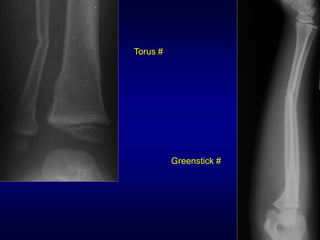

Torus #

Greenstick #

Bowing #

Orientation of the fracture line

Torus # Greenstick #